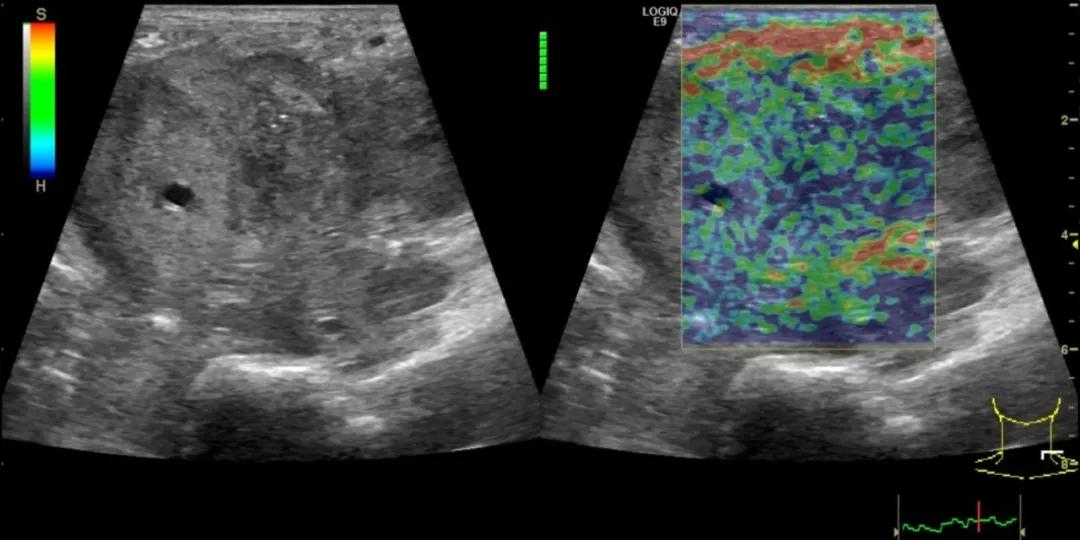

第二例是食管癌患者,术后半年余锁骨上固定淋巴结可触及肿大,疼痛非常明显,系统治疗后无缓解,患者希望通过局部处理缓解症状。造影显示强化信号明显,结节部分区域坏死,故主要针对强化区域从后向前的逐层的消融,皮下进行液体隔离减少烫伤。热消融后影像显示血流增强消失,弹性、硬度增高,一个月后复查显示充盈缺损,完全消融,疗效远超预期。

(病例2图例)